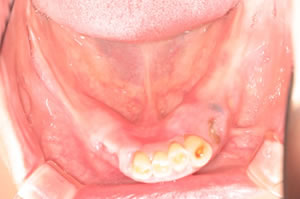

奥歯に骨がないので、オールオン4で即時荷重(インプラント手術をした日に仮歯がはいる)をおこないました。